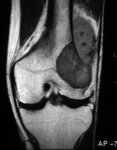

Magnetic resonance imaging, coronal view; osteosarcoma of distal femur showing low-intensity signal; T1-weighted image; actual intraosseous and extraosseous tumor extent is also appreciated

Personal collections of Dr Michael J. Klein and Dr Luminita Rezeanu